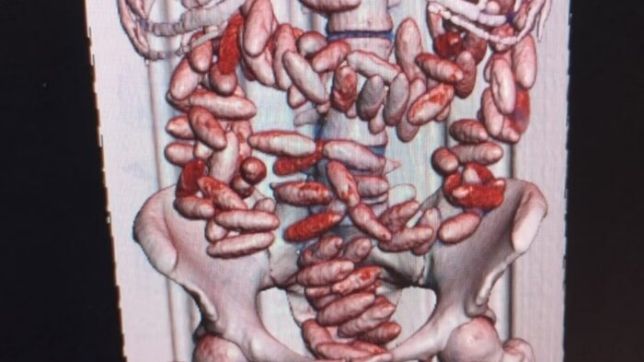

Ainda segundo a PF, os passageiros demonstraram bastante nervosismo, inquietação e impaciência e acabaram confessando que estavam transportando em seus corpos cápsulas de cocaína, sendo 100 cápsulas no organismo do homem e 114 cápsulas no corpo da mulher.

Cada cápsula possui aproximadamente 12g, o que perfaz um total de 2.6 kg de cocaína sendo transportados no organismo dos dois presos. De acordo com a PF, caso uma cápsula se rompa, a pessoa pode sofrer uma overdose e morrer.

Eles foram conduzidos para um hospital público e já expeliram as 120 cápsulas e ainda precisam ser retiradas 94 cápsulas. Assim que receberem alta médica serão conduzidos para a Sede da Polícia Federal para prestarem depoimentos e em seguida passarão por audiência de custódia.